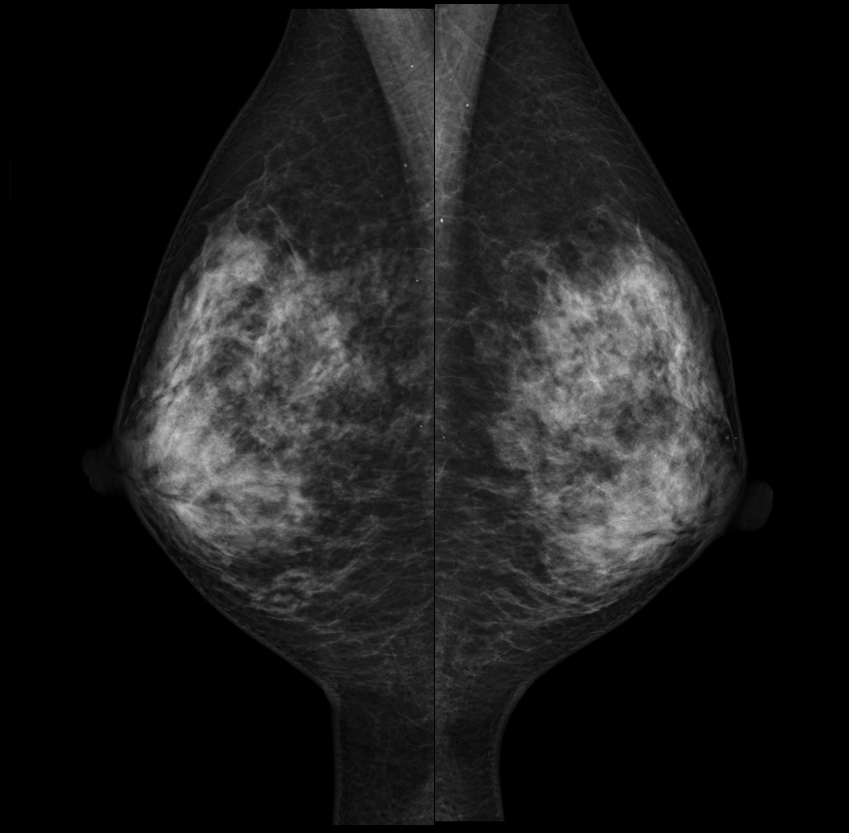

マンモグラフィ

当院では富士フィルムメディカル社製AMULET Innovalityを設置しています。

マンモグラフィは乳房専用の撮影装置を使用して行う検査で、ご自身で触知できないような早期の乳がんの発見に有用性が認められています。乳房を圧迫し薄くのばして撮影します。撮影時に痛みを伴うことがありますが、被ばく低減や質のよい画像を得る為にご協力の程よろしくお願いいたします。何かご不明な点がありましたら、ご遠慮なくお声がけください。

日本乳がん検診精度管理中央機構が定める「マンモグラフィ検診 施設・画像認定」を取得しています。これは質の高い乳がん検診を提供できると認められた施設にのみ与えられるものです。また、「検診マンモグラフィ撮影認定診療放射線技師」の資格を取得した技師を中心に撮影は全て女性技師が対応しています。